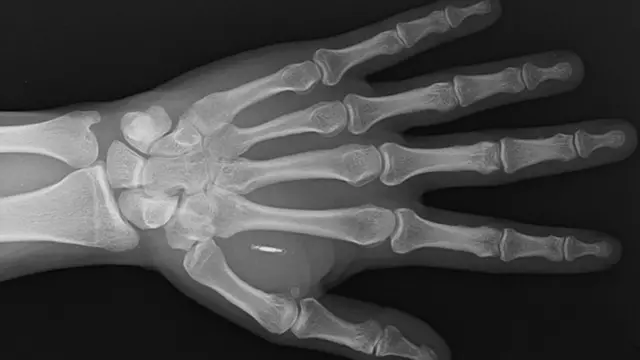

2019లో ప్యాట్రిక్, కాంటాక్ట్లెస్ పేమెంట్ మైక్రోచిప్ను తన చేతిలో అమర్చుకున్నారు. దీని కారణంగానే ఆయన చేయి పెట్టగానే చెల్లింపులు జరిగిపోతున్నాయి.

వాలెట్మోర్ చిప్, ఒక గ్రామ్ కంటే తక్కువ బరువు ఉండి బియ్యం గింజ కంటే కాస్త పెద్ద పరిమాణంలో ఉంటుంది. ఇందులో ఒక చిన్న మైక్రోచిప్, బయో పాలిమర్లో నిక్షిప్తమైన యాంటెన్నా ఉంటాయి. బయోపాలిమర్ సహజ పదార్థం. ఇది ప్లాస్టిక్ను పోలి ఉంటుంది.

ఇది పూర్తిగా సురక్షితమైనదని, రెగ్యులేటరీ ఆమోదాన్ని పొందిందని, శరీరంలో అమర్చిన క్షణం నుంచే పనిచేస్తుందని, ఒక్కచోటే స్థిరంగా ఉండిపోతుందని పప్రోటా చెప్పారు. దీనికి బ్యాటరీ లేదా ఇతర శక్తి వనరుల అవసరం లేదు. ఇప్పటివరకు 500లకు పైగా చిప్లను విక్రయించినట్లు వాలెట్మోర్ తెలిపింది.

వాలెట్మోర్ కంపెనీ, ఈ చిప్ కోసం నియర్ ఫీల్డ్ కమ్యూనికేషన్ (ఎన్ఎఫ్సీ) అనే సాంకేతికతను వినియోగించింది. స్మార్ట్ఫోన్లలోని కాంటాక్ట్లెస్ పేమెంట్ల కోసం కూడా ఇదే సాంకేతికత వాడతారు. ఇతర చెల్లింపు పరికరాలు రేడియో ఫ్రీక్వెన్సీ ఐడెంటిఫికేషన్ (ఆర్ఎఫ్ఐడీ) అనే సాంకేతికతపై ఆధారపడి ఉంటాయి. డెబిట్, క్రెడిట్ కార్డుల్లో ఉండే సాంకేతికతను ఇది పోలి ఉంటుంది.